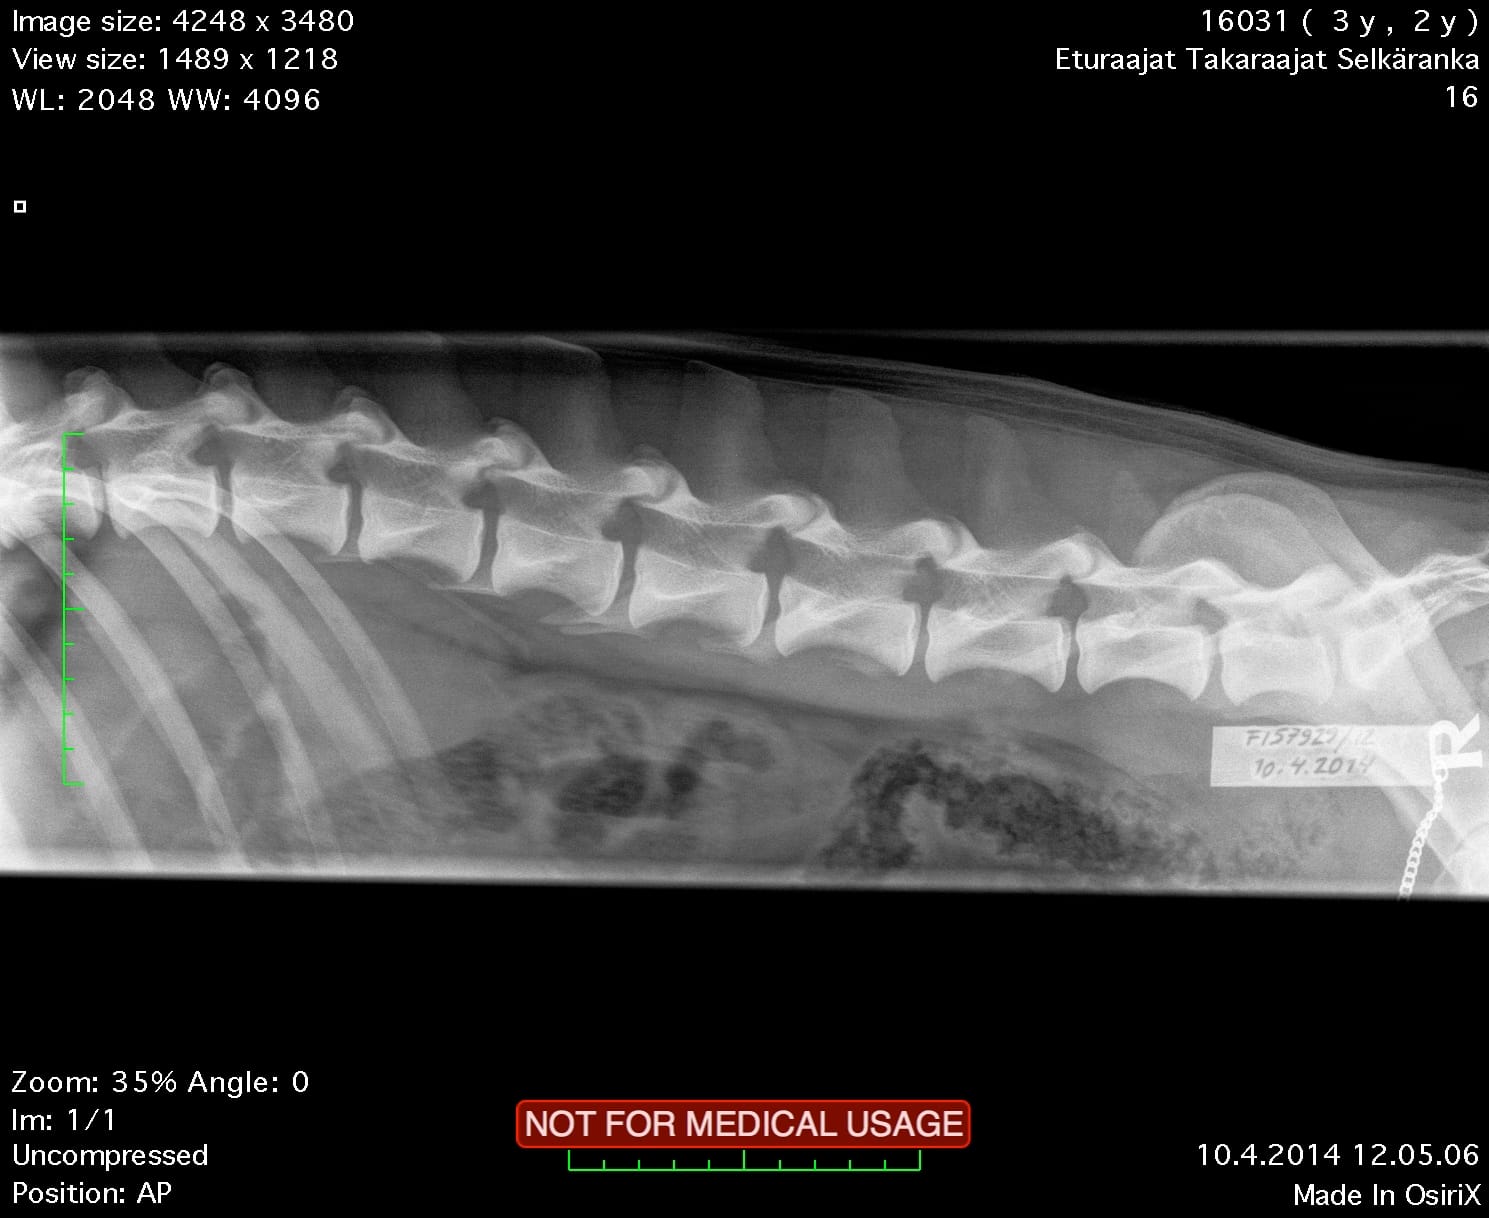

| Shoulders: | clear | |

| Spine: | SP0, LTV4 (8 lumbosacral vertebrae) | |